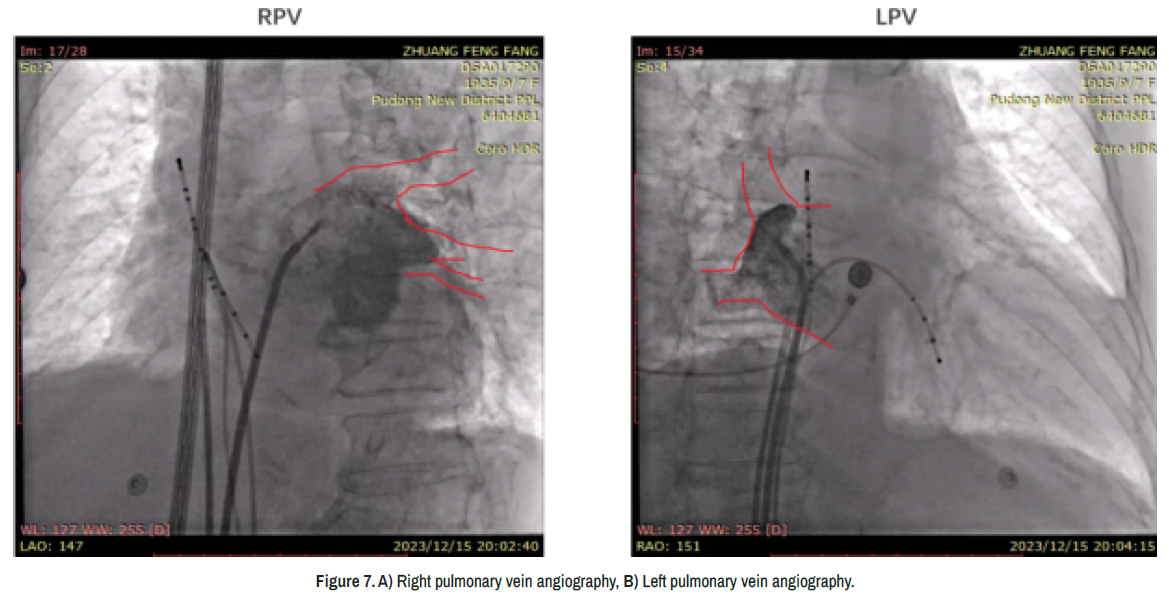

Because of the patient’s unique anatomical considerations arising from dextrocardia, a Johnson & Johnson adjustable bend coronary sinus electrode, which was designed for typical cardiac geometries, could not be navigated into the patient’s coronary sinus. Consequently, it was positioned in the conventional right atrium (actually the patient’s left atrium) for atrial potential monitoring (Figure 7).

clinical-case-reports-angiography

Figure 7. A) Right pulmonary vein angiography, B) Left pulmonary vein angiography. Figure 8.